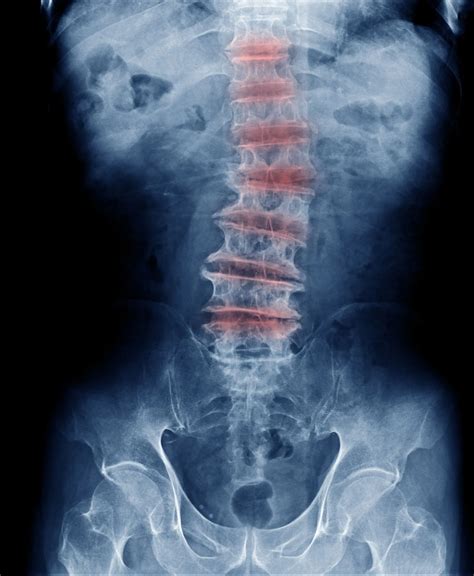

Multilevel Degenerative Disc Disease

Multilevel degenerative disc disease (DDD) is a condition that affects multiple spinal discs, leading to significant pain and mobility issues. This progressive condition occurs when the discs between the vertebrae in the spine degenerate over time, causing a range of symptoms that can severely impact daily life. Understanding the causes, symptoms, diagnosis, and treatment options for multilevel degenerative disc disease is crucial for managing this condition effectively.

• Imaging Tests: Diagnostic imaging such as X-rays, MRI, or CT scans to visualize the spinal discs and vertebrae.